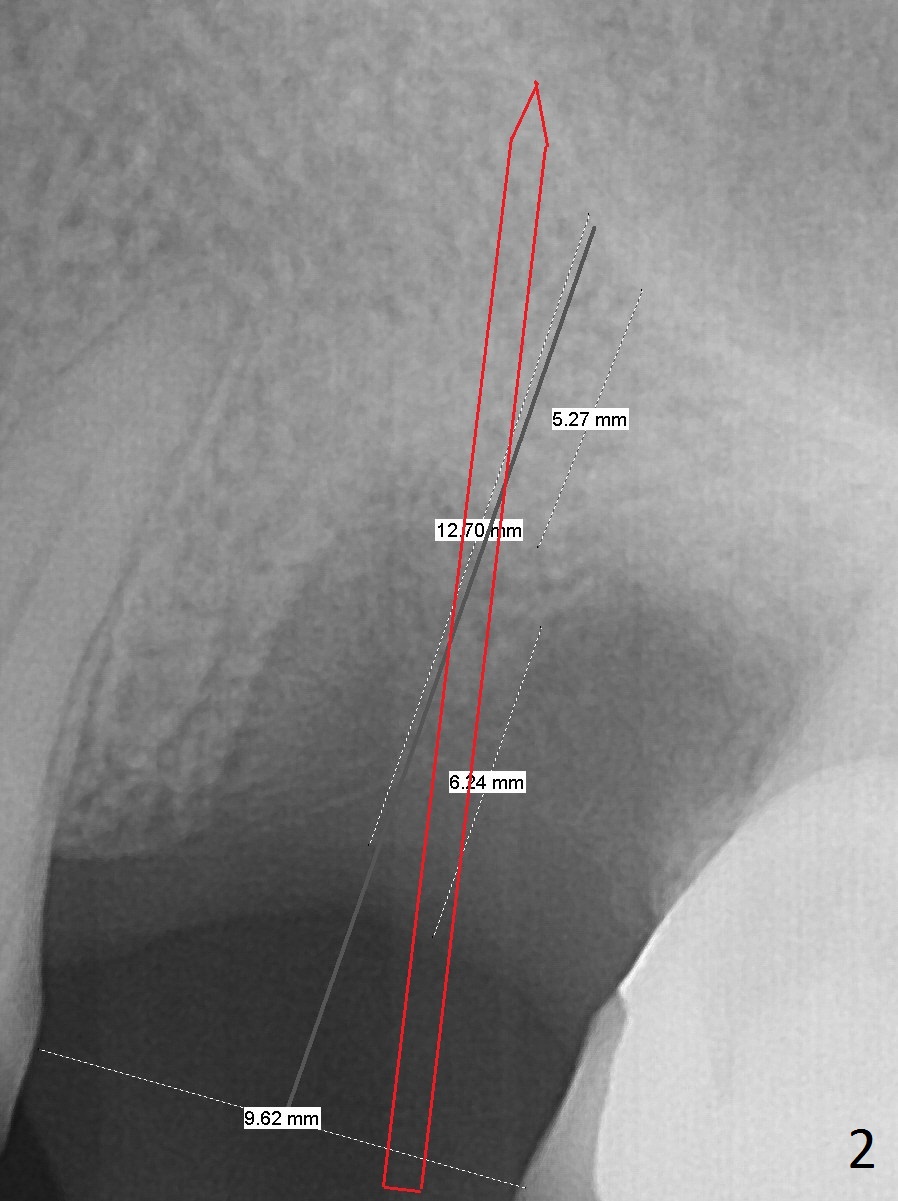

A 44-year-old woman will return to clinic for #14 implant placement 2.5 months post extraction (Fig.1).  The tooth used to have persistent fistula.  The bone density appears to be low coronally.  To compensate for the sloped sinus floor (arrowheads), start osteotomy as mesial as possible (Fig.2 red arrow) either with Magic Expander or Drill and place an implant as high as possible (Fig.3).  If there is buccal plate defect, place the implant as palatal and deep as possible.  Use Metronidazole routinely for sinus cases.